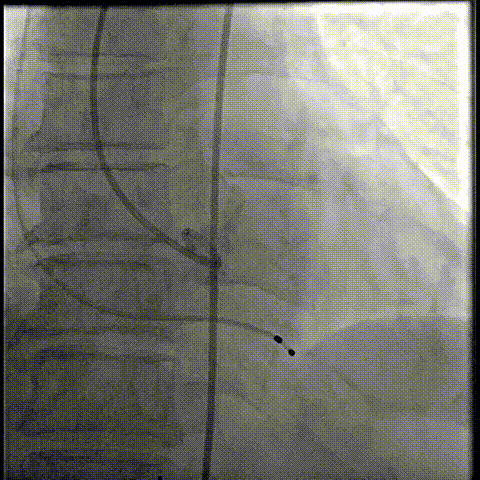

20球囊预扩

器械过弓柔顺